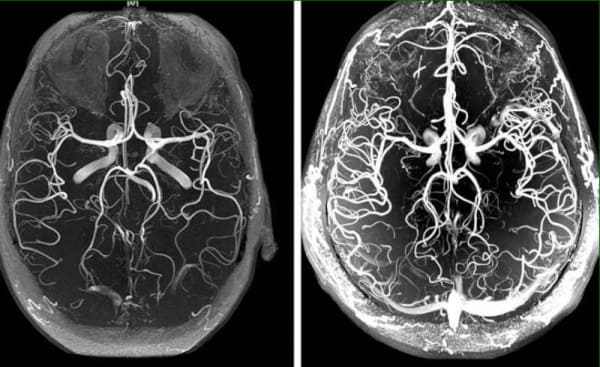

Мия томирларининг ангиодистонияси-бу қон томир тонуси ва мия тўқималарида нормал қон айланиши бузилган патологик ҳолат. Ушбу мақолада унинг сабаблари , механизмлари ва аломатлари ҳақида ўқишингиз мумкин. Шунингдек, ушбу маккор касалликнинг даҳшатли асоратлари ва ҳамма учун мавжуд бўлган даволанишга замонавий ёндашув ҳақида.

Мия томирларининг ангиодистонияси организм томирларининг холестерин – атеросклероз билан умумий "ифлосланиши" нинг дастлабки белгисидир. Миянинг томирлари енг нимжон ва нозикдир, шунинг учун улар биринчи бўлиб урилади.

Мия томирларининг қон айланишини даволаш бутун тананинг томирларини тўпланган аралашмалардан тозалашга асосланган. Холестерин плиталари, қон қуйқалари ва калций оҳак каби.

Қон айланишини тиклаш ва қон томирларини тозалаш мураккаб жараёндир. Бу тананинг барча томирларига таъсир қилади ва ҳаёт сифатини кўп марта яхшилайди.